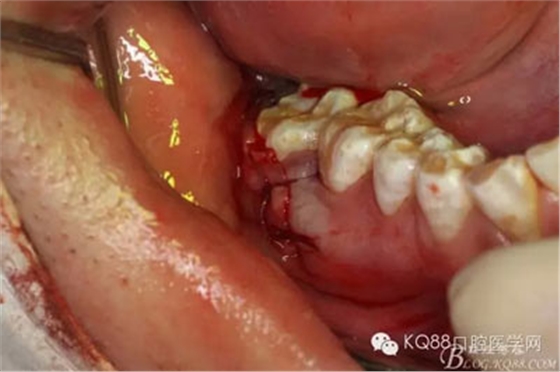

圖6.切開(kāi)、翻瓣

圖7.粘膜瓣似乎粘連,非常難翻,結(jié)果48還在骨頭里,頰側(cè)骨壁沒(méi)缺失呀,CBCT有問(wèn)題?

圖8.不管它,眼見(jiàn)為實(shí),去骨,發(fā)現(xiàn)48與周圍骨質(zhì)沒(méi)有界限,幾乎完全粘連

圖9.不斷的耐心去骨,發(fā)現(xiàn)48被下方的囊性改變趕到舌側(cè)。